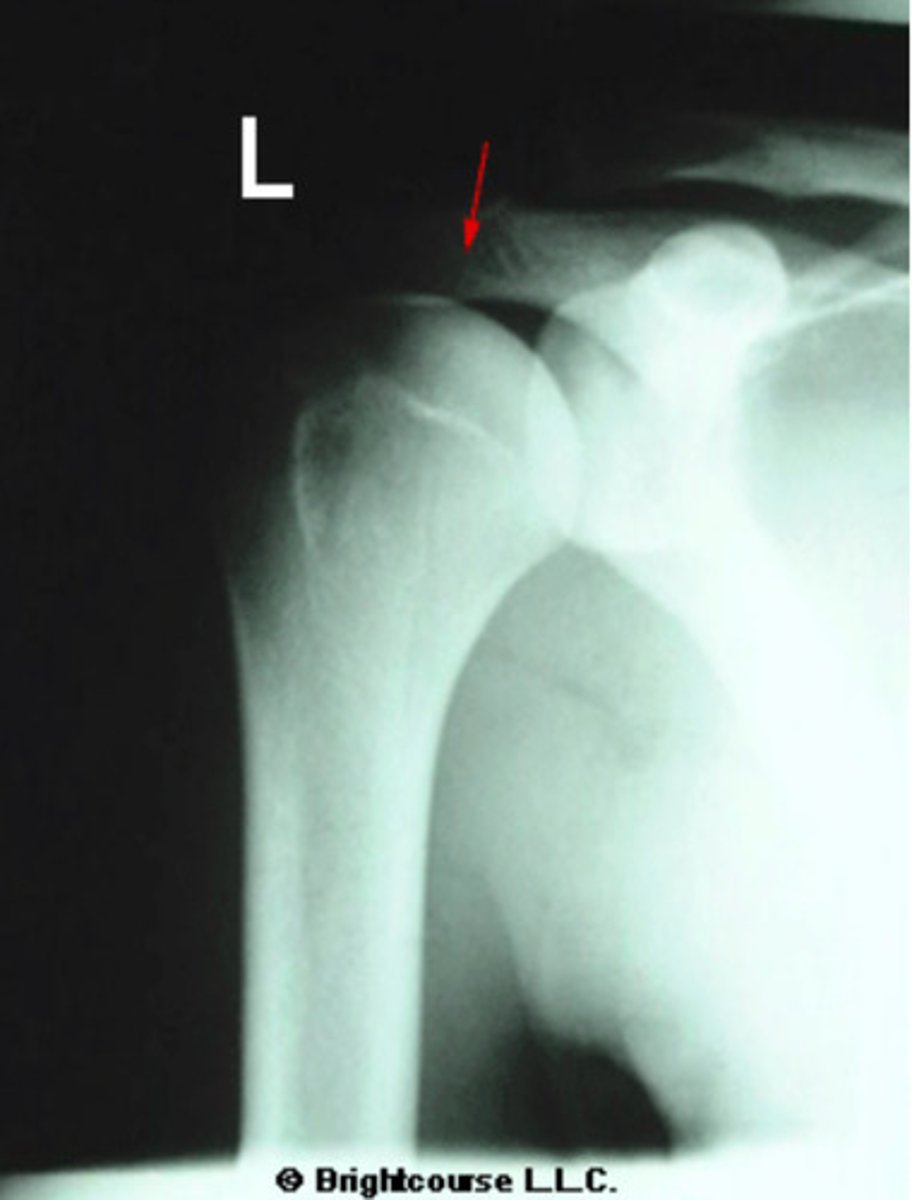

Acromion process

What is being pointed out by the arrow in the image?